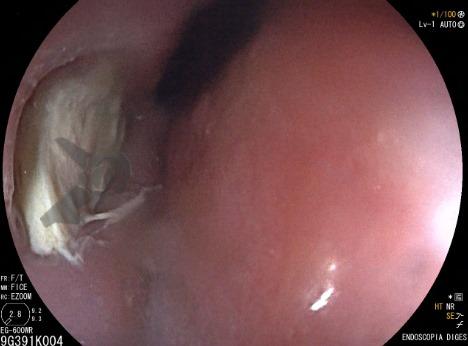

Paciente feminina, 59 anos, portadora de fibrilação atrial paroxística, foi submetida a ablação térmica para tratamento da arritmia. Encontrava-se assintomática até que dez dias após o procedimento iniciou com quadro de dor torácica e sintomas de refluxo. Endoscopia digestiva alta demostrou o seguinte achado: